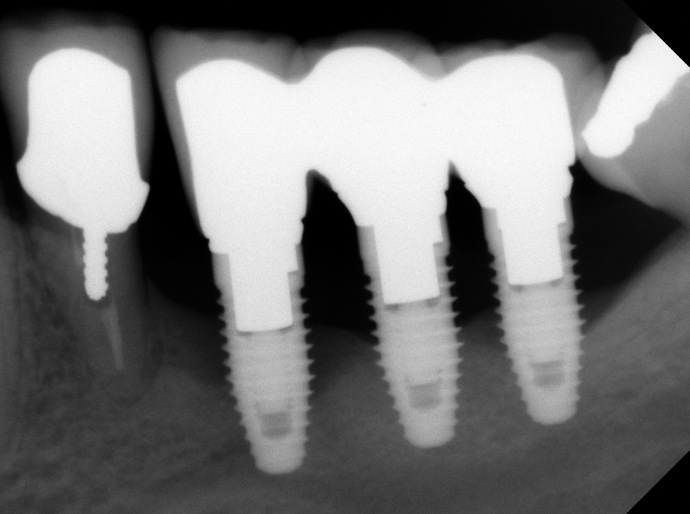

Fig 2. Radiograph suggested moderate bone loss around the implants.

Figure 2